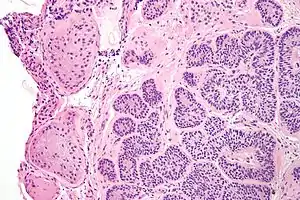

Sertoli cell nodules are unencapsulated nodules that consist of:[1][2][3]

- cells arranged in well-formed tubules (that vaguely resemble immature Sertoli cells), with

- bland hyperchromatic oval/round nuclei that are stratified, and

- may contain eosinophilic (hyaline) blob in lumen (centre).

Micrograph of a Sertoli cell nodule. H&E stain.